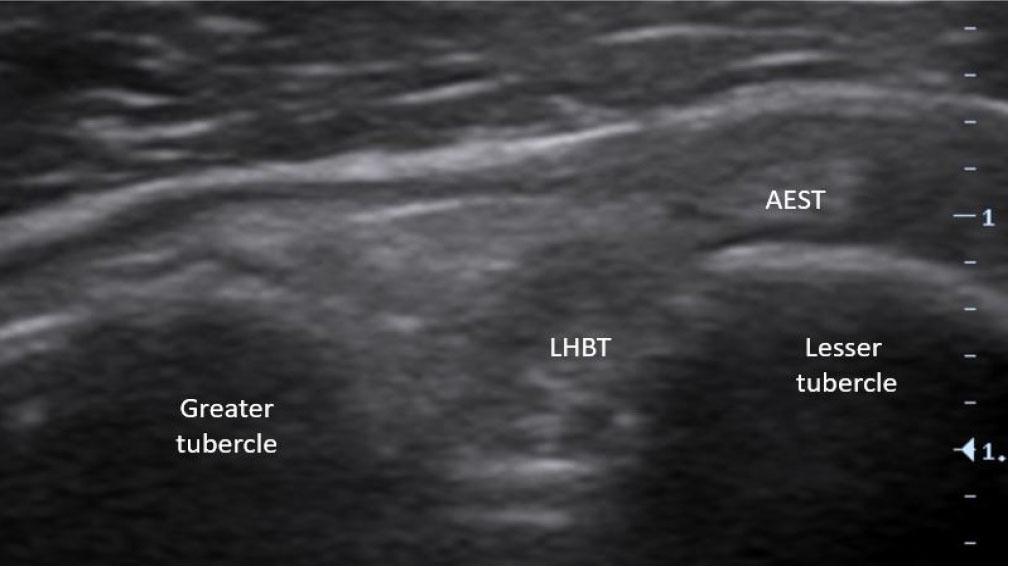

At the level of the rotator interval, AEST was assessed for echogenicity, intrasubstance tears, and its relationship to the LHBT and subscapularis tendon (Fig. 3), while the supraspinatus was checked for tear-related changes. AEST was then examined at the intertubercular groove to determine its position (intragroove, subluxation, dislocation, medial dislocation; Fig. 4), along with LHBT and subscapularis integrity. The remaining shoulder structures, including the other rotator cuff tendons and the glenohumeral and acromioclavicular joints, were systematically reviewed. The findings are summarized in Tab. 1.

A second proposed classification was developed to describe AEST positioning within the rotator interval (Fig. 3 and Fig. 11). Importantly, the relationship of AEST at the intertubercular groove level depends on the degree of its detachment from the supraspinatus tendon and whether subluxation or dislocation is present (see AEST and LHBT relationship).

The most frequent abnormality was AEST dislocation with preserved intragroove LHBT, observed in six of 19 cases (31.6%) (Fig. 15). LHBT dislocation in the presence of intragroove AEST was identified in three cases (15.8%) (Fig. 16), while AEST intragroove subluxation with preserved LHBT alignment was found in another three cases (15.8%) (Fig. 17). Combined pathology included two cases (10.5%) of concomitant AEST and LHBT dislocation (Fig. 18), one case (5.3%) of LHBT subluxation with intragroove AEST, and one case (5.3%) of concomitant AEST and LHBT subluxation (Fig. 19). In four cases (21.1%), no abnormalities were observed.

Aponeurotic expansion of the supraspinatus tendon (AEST) intragroove subluxation with preserved long head of the biceps tendon (LHBT) alignment in the right shoulder (AEST–LHBT classification: Ia, case 11)